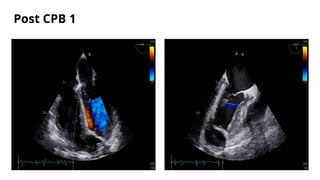

Post CPB 1

o Going on CPB - U/E,

o CPB 1- CABG * 2G, VSR patch

o Coming off CPB1 - NSR with supports Levosimendan@0.075, Adr@0.05 & Vaso @0.0003

o Post CPB 1 TEE- initially showed a color jet within the RV in the transgastric images which were

not traced to LV in the midesophageal images. Continued imaging revealed this colour jet to be

getting prominent.

o PA sO2 - 71%, RA sO2 - 67%

o Went on CPB-2 @ protamine 75%

o For CPB 2- Inj.Heparin 5mg/kg repeated.